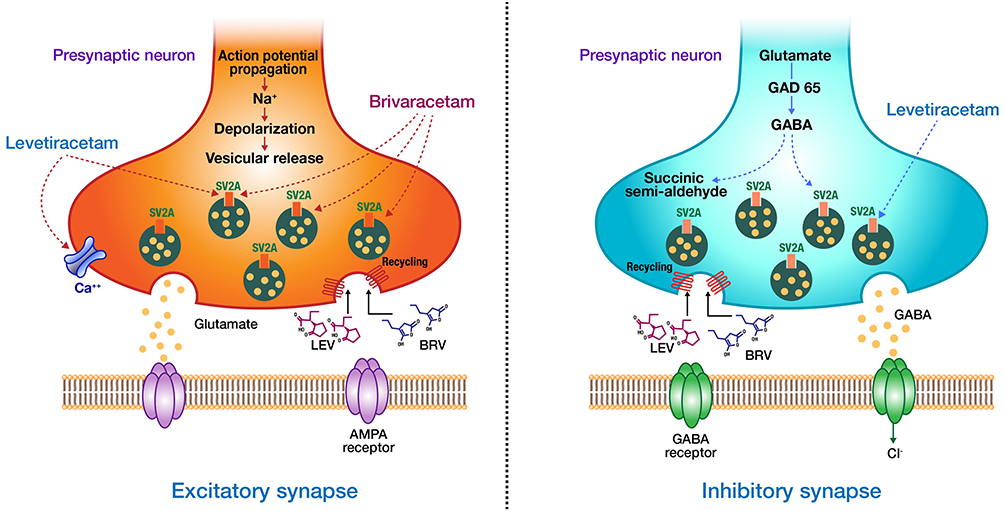

Механизмы действия антимикотиков: схемы и изображения